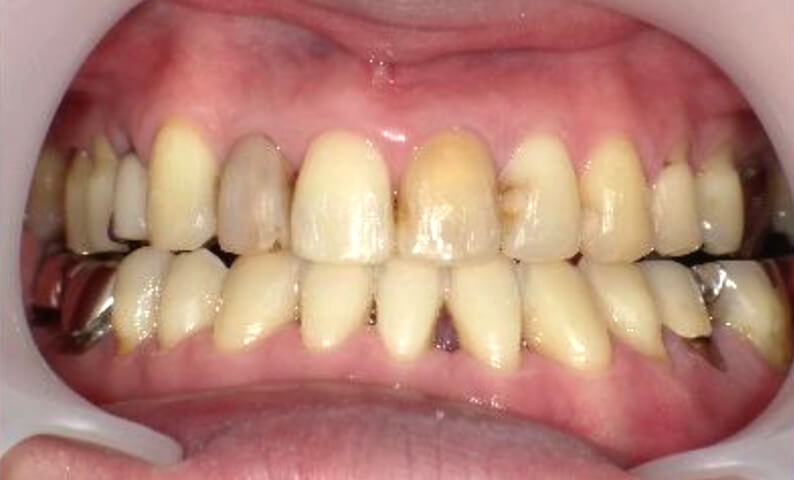

症例_003 下顎だけの部分矯正

治療期間:10ヶ月金額:24万円+税女性前歯のガタガタ下の前歯だけ上顎は補綴治療中

| Before | After |